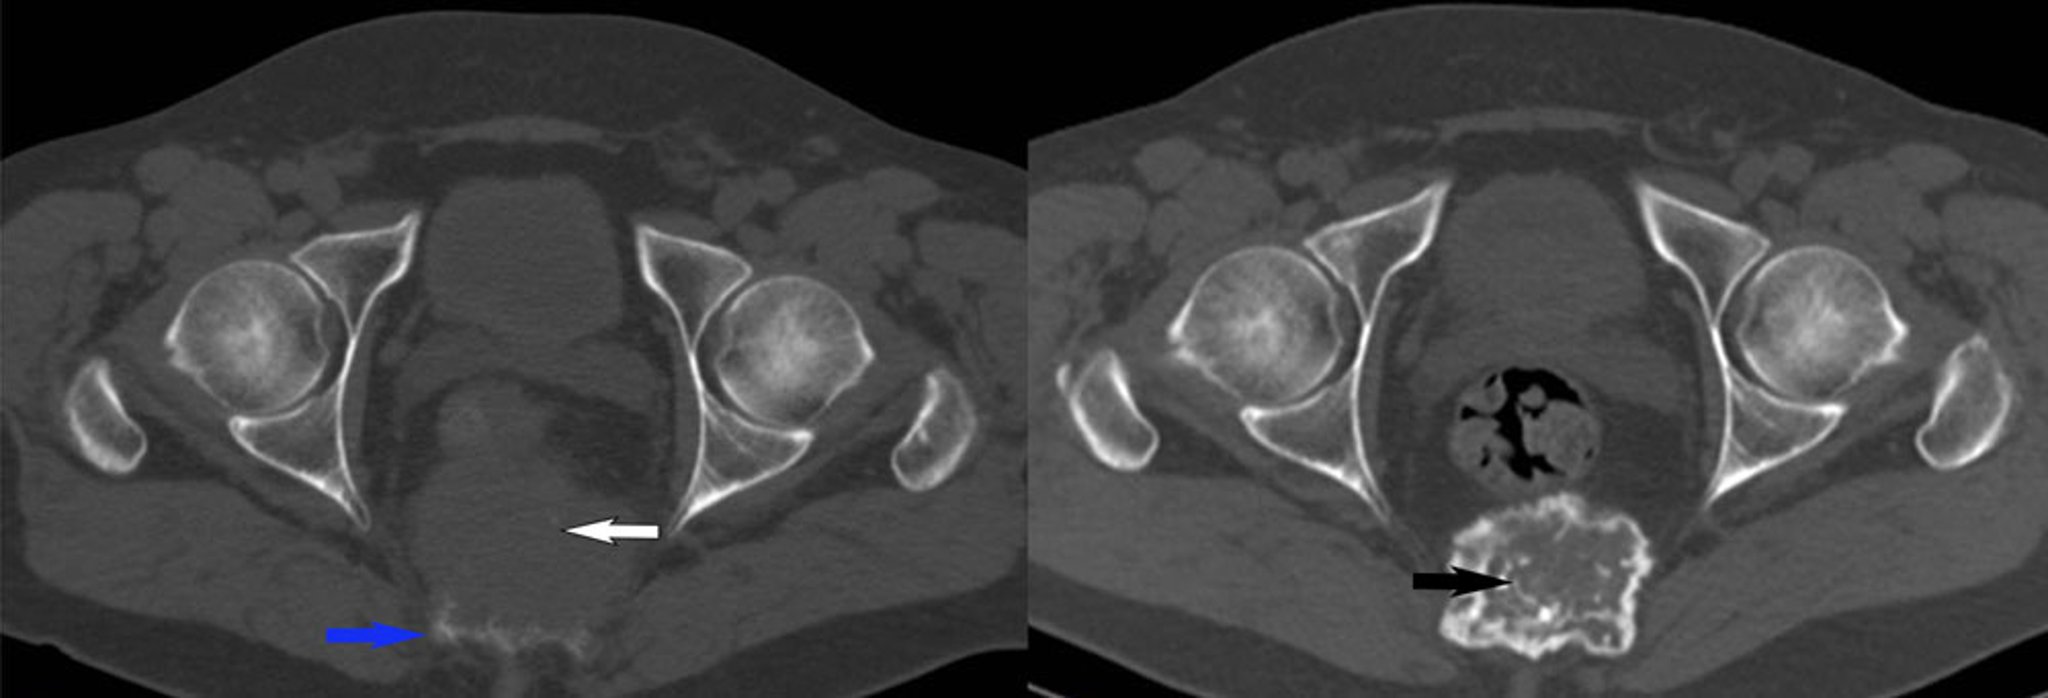

Giant Cell Tumor of Bone (CT Scan)

This axial CT scan (left) shows a lytic lesion of the sacrum (bottom blue arrow) with anterior soft tissue mass (top white arrow). A biopsy confirmed giant cell tumor of bone. Following denosumab treatment, the follow-up CT scan (right) shows progressive ossification of the tumor (bottom black arrow) without an increase in size.

Image courtesy of Michael J. Joyce, MD, and Hakan Ilaslan, MD.